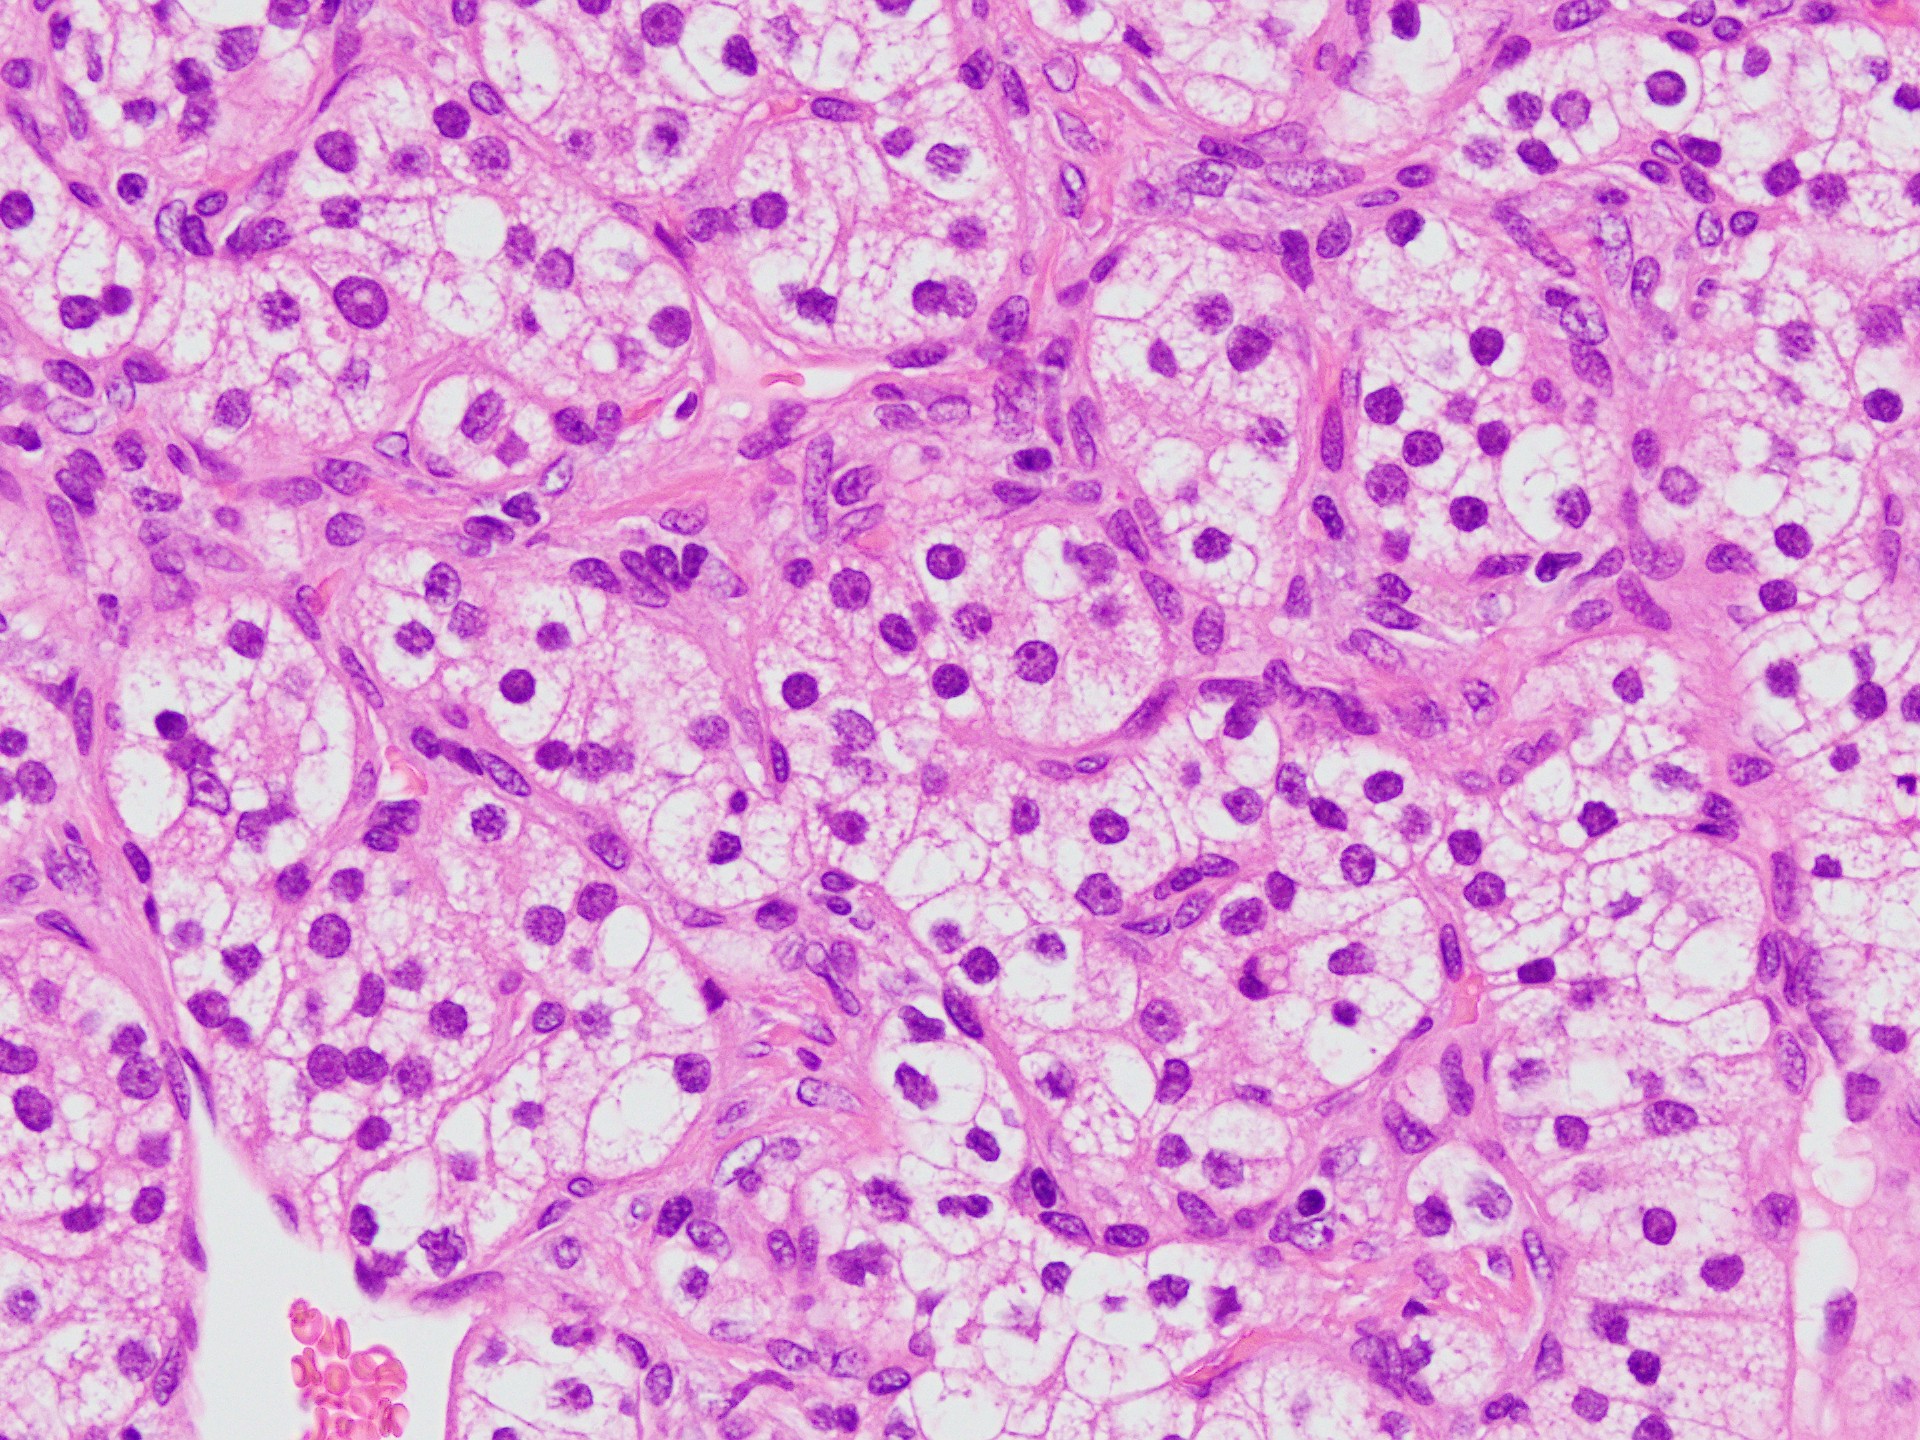

上皮性結合を示す細胞集塊が見られます。

構成細胞は、淡明で豊富な細胞質を有しているのが特徴です(細胞質内にグリコーゲン・脂質を有している)。

核は比較的小型で円形から楕円形を示し、核形の不整が認められます。

また、核小体が明瞭な異型細胞も観察されます。

小型類円形核と淡明な胞体を有する細胞が繊細な線維血管網宙に胞巣を形成しています。